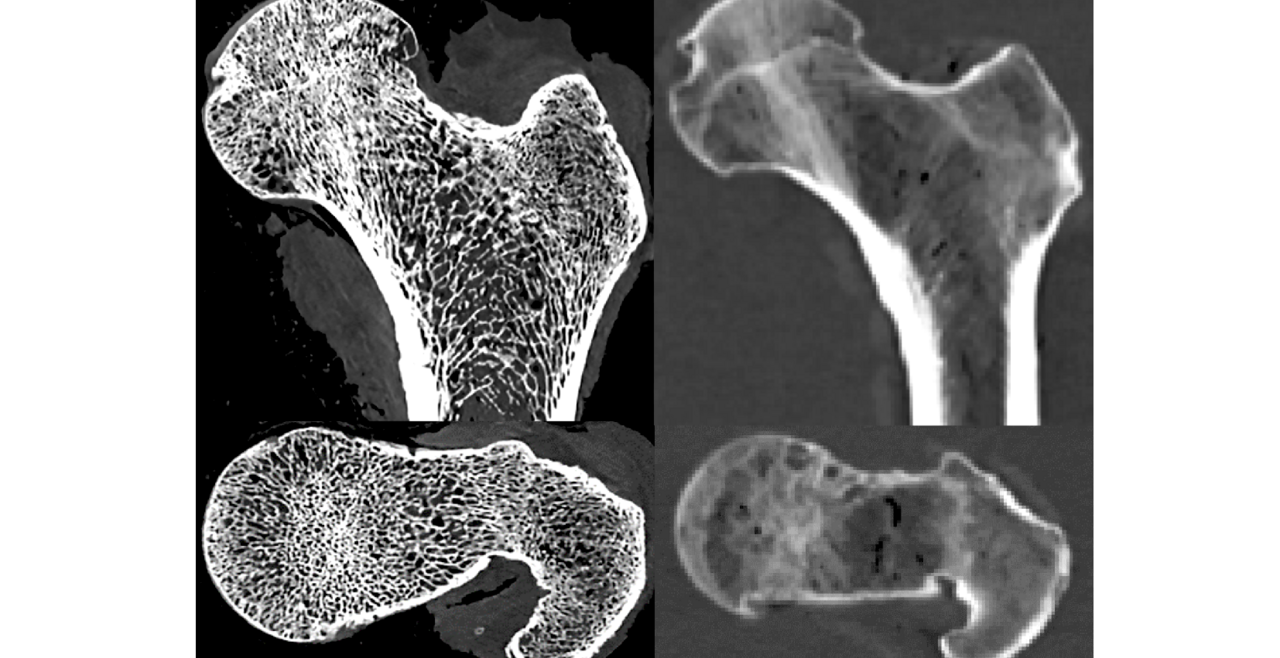

Bone changes in spaceflight